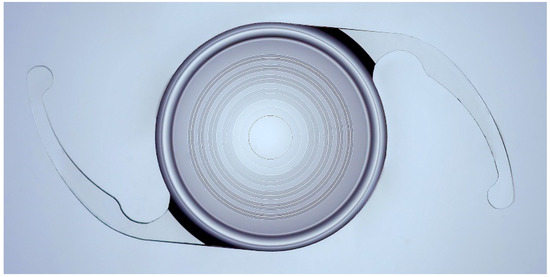

All patients were implanted with the AsqelioTM trifocal TFLIO130C model IOL (AST Products, Inc., Billerica, MA, USA). This IOL has a bi-aspheric geometry with a posterior diffractive optic design (15 rings within the central 4.5 mm) in its 6.0 mm-diameter optical zone (Figure 1). It has a total diameter of 13.0 mm and provides an addition for near distances of +3.30 D and +2.20 D for intermediate distances. The lens is built in powers ranging from +5.00 to +34.00 D in 0.50 D increments, with a C-Loop platform and a light distribution among its foci of 50% for distance, 24% for intermediate, and 26% for near. It is made of a soft hydrophobic acrylic material (glistening-free) with a refractive index of 1.50, Abbe number of 50, and spherical aberration of −0.27 microns.

Figure 1.

AsqelioTM Trifocal TFLIO130C.